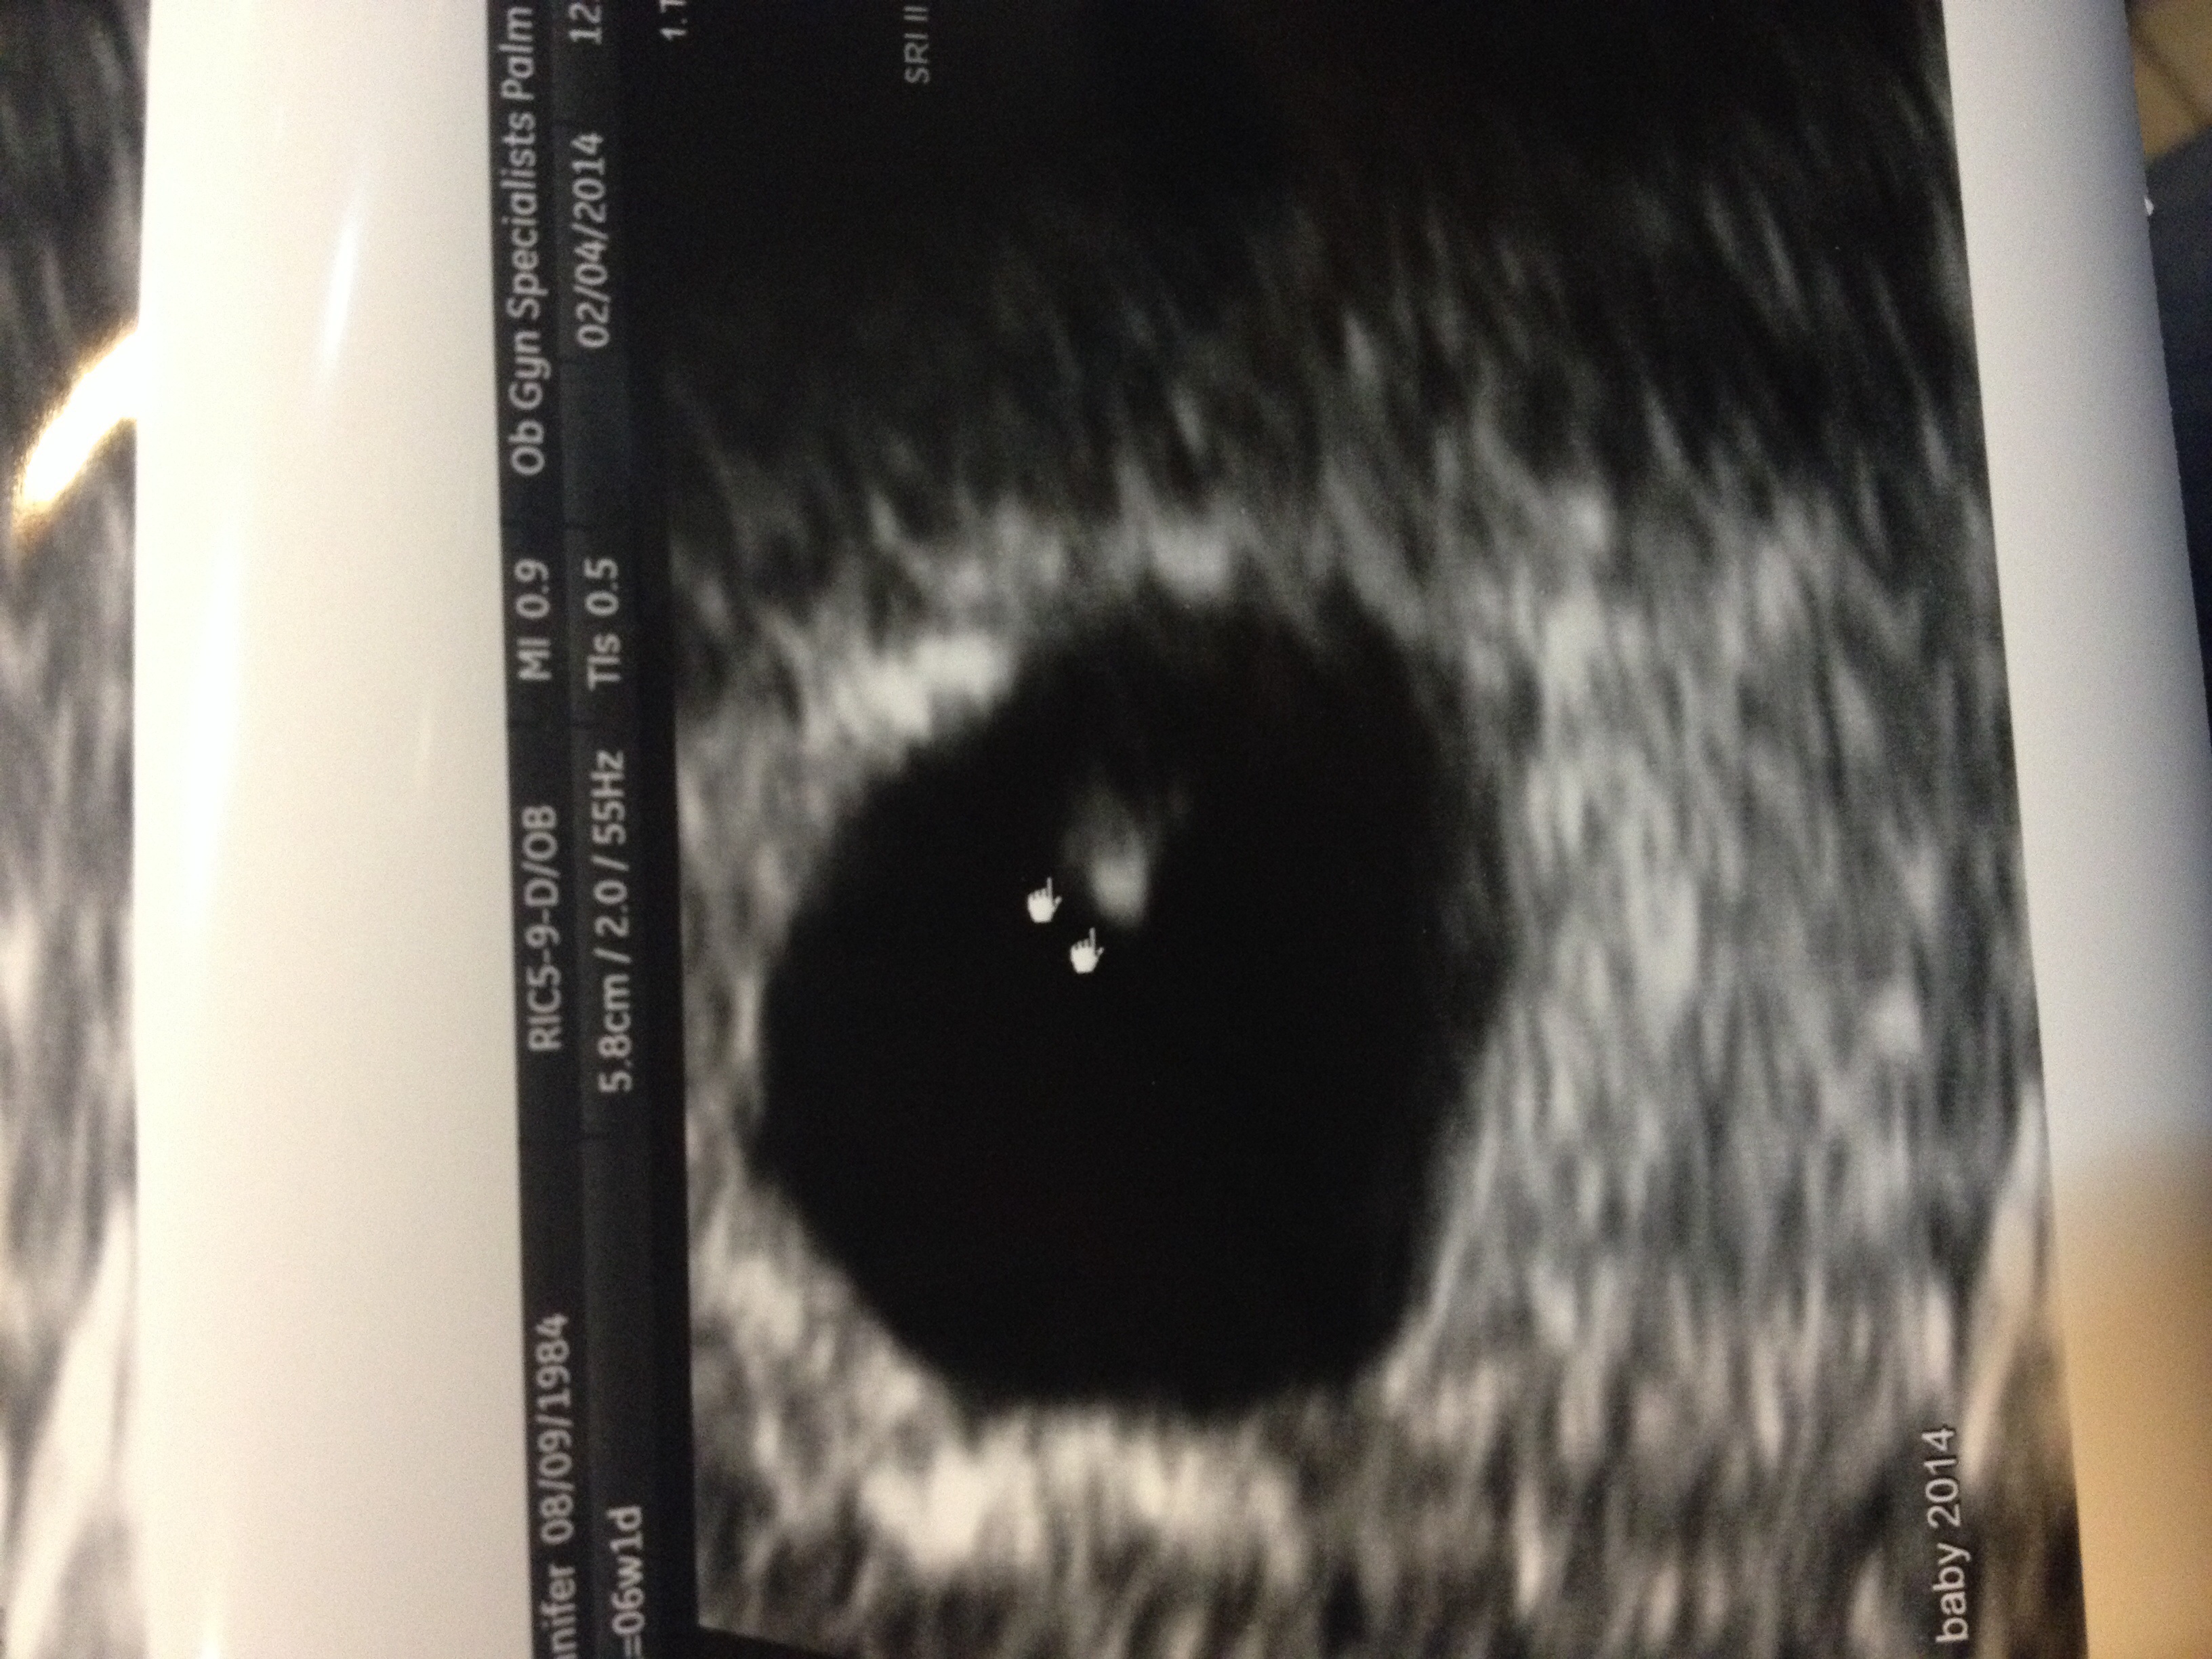

• I am 6 weeks and 2 days went in for my first doctors appointment today :) saw our little rice bean lol as my husband calls it. No heartbeat yet. Have to go back in two weeks for that. Here is my ultra sound. We are so excited!!

View Full Size Image